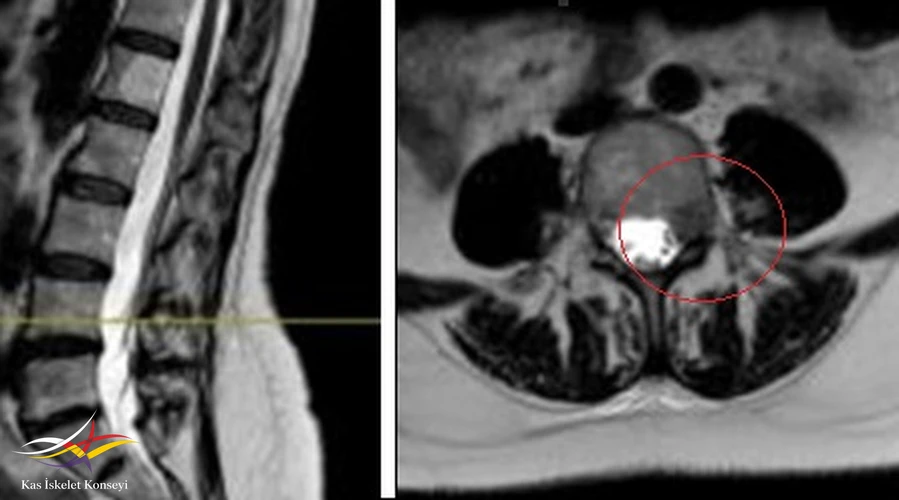

- Lomber MRG: Disklerde yükseklik kaybı veya anüler yırtık yok. L4-5 te solda forameni içinde, kök üzerinde şüpheli bir lezyon lezyon saptanması üzerine yapılan kontrastlı MRG'de lezyonda yoğun ve homojen kontrast tutulumu görüldü ve kitle lehine yorumlandı.

Resim 1. Lomber MRG'de L4-5 seviyesinde sol nöral foramende kitle imajı görülüyor.

Resim 2. Kontrastlı MRG'de lezyonun yoğun kontrast tuttuğu görülmekte.